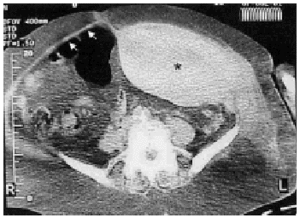

Figura 1. Tomografía computarizada del abdomen, en la que se observa un hematoma gigante del músculo recto izquierdo (*) y oblicuos junto a ausencia de líquido libre abdominal. Obsérvese, para su comparación, el tamaño normal del músculo recto derecho (flechas).

Una mujer de 80 años con antecedentes de asma y miocardiopatía hipertensiva acudió al hospital por presentar tos seca, disnea y palpitaciones. Seguía tratamiento con torasemida, quinapril y troxerutina. La exploración física reveló sibilancias diseminadas, ritmo cardíaco irregular y edemas maleolares, e insuficiencia venosa periférica. La temperatura fue de 36,8 ºC, la presión arterial de 160/95 mmHg y la frecuencia cardíaca de 150 lat/min. La analítica de ingreso únicamente mostró una mínima elevación de los valores de creatinina (1,2 mg/dl) y de urea (61 mg/dl). Tras establecerse el diagnóstico de bronquitis aguda con broncospasmo y fibrilación auricular aguda, la enferma fue tratada con ácido acetilsalicílico, enoxaparina subcutánea (1 mg/kg/12 h), digoxina, furosemida, codeína, diltiazem, metilprednisolona, levofloxacino y aerosoles de broncodilatadores. Al tercer día de ingreso, la paciente fue trasladada a la unidad de cuidados intensivos por dolor abdominal intenso tras accesos repetidos de tos e hipotensión arterial de 80/50 mmHg. La palpación abdominal reveló la presencia de una masa redondeada, dolorosa y no pulsátil en la zona infraumbilical izquierda. La analítica puso de manifiesto un descenso de los valores de hemoglobina desde 13,3 a 9,3 g/dl, y del hematocrito del 40,2 al 28,1%, así como un ligero deterioro de la función renal (creatinina de 1,6 mg/dl y urea de 78 mg/dl) y una alteración de la coagulación (actividad de protrombina de 14,5 s y tiempo de tromboplastina de 53,5 s). Una tomografía axial computarizada abdominal evidenció un HVR gigante y ausencia de sangrado intraperitoneal (fig. 1). La enoxaparina y el diltiazem fueron suspendidos, y la paciente fue tratada con fluidos, concentrados de hematíes (9 unidades) y factores del complejo protrombínico. La paciente tuvo una evolución favorable sin necesidad de tratamiento quirúrgico.